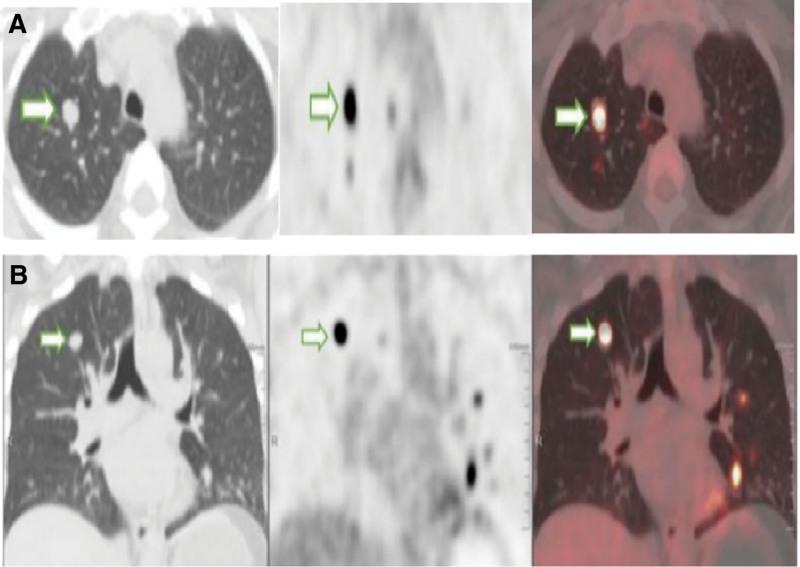

In clinical settings, an estimated 10% differentiated thyroid cancer (DTC) cases become radioactive iodide refractory (RAIR), which lack a molecular marker and have fewer treatment selections. A higher uptake of 18F-fluorodeoxyglucose (18F-FDG) might indicate poor prognosis for DTC. This study aimed to evaluate the clinical value of 18F-FDG psitron emission tomography/computed tomography (PET/CT) for the early diagnosis of RAIR-DTC and high-risk DTC. A total of 68 DTC patients were enrolled and underwent 18F-FDG PET/CT for the detection of recurrence and/or metastasis. 18F-FDG uptake was evaluated in patients with different postoperative recurrence risks or TNM stages and compared between RAIR and non-RAIR-DTC based on its maximum standardized uptake value and tumor/liver (T/L) ratio. The final diagnosis was judged by histopathology and follow-up data. Of 68 DTC cases, 42 were RAIR and 24 non-RAIR, with 2 not determined. A total of 263 of 293 lesions detected on 18F-FDG PET/CT were confirmed to be locoregional or metastatic after follow-up. The T/L ratio was significantly higher for RAIR than for non-RAIR (median 5.18 vs 1.44; P < .01) and also significantly higher in postoperative patients at high-risk of recurrence than at low to medium risk (median 4.90 vs 2.16; P < .01). 18F-FDG PET/CT exhibited a sensitivity of 83.3% and specificity of 87.5% for identifying RAIR, with a cutoff T/L value of 2.98. 18F-FDG PET/CT has the potential to diagnose RAIR-DTC early and identify the high-risk DTC. The T/L ratio is a useful parameter for the detection of RAIR-DTC patients.

在临床环境中,约有 10%的分化型甲状腺癌(DTC)病例会出现放射性碘难治(RAIR),这部分病例缺乏分子标志物,治疗选择较少。DTC 患者 18F-氟代脱氧葡萄糖(18F-FDG)摄取较高可能预示预后不良。本研究旨在评估 18F-FDG 正电子发射断层扫描/计算机断层扫描(PET/CT)对 RAIR-DTC 和高危 DTC 的早期诊断价值。共纳入 68 例 DTC 患者,均行 18F-FDG PET/CT 以检测复发和/或转移。根据最大标准化摄取值(SUVmax)和肿瘤/肝脏(T/L)比值,对不同术后复发风险或 TNM 分期的患者进行 18F-FDG 摄取评估,并根据 SUVmax 和 T/L 比值比较 RAIR 和非 RAIR-DTC 患者间的摄取差异。最终诊断通过组织病理学和随访数据判断。68 例 DTC 患者中,42 例为 RAIR,24 例为非 RAIR,2 例未确定。18F-FDG PET/CT 共检测到 293 个病灶,其中 263 个经随访证实为局部或远处转移。RAIR 患者的 T/L 比值明显高于非 RAIR(中位数 5.18 比 1.44;P < .01),且术后高复发风险患者的 T/L 比值也明显高于低至中复发风险患者(中位数 4.90 比 2.16;P < .01)。18F-FDG PET/CT 诊断 RAIR 的敏感度为 83.3%,特异度为 87.5%,截断 T/L 值为 2.98。18F-FDG PET/CT 具有早期诊断 RAIR-DTC 和识别高危 DTC 的潜力。T/L 比值是检测 RAIR-DTC 患者的有用参数。